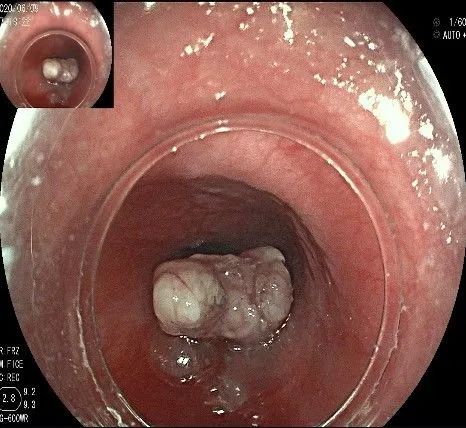

向下一直切开至齿状线处,白色为鳞状上皮,红色为腺上皮,颗粒样的部分,就是炎性息肉。切开后可见瘤体为白色,表面有血管网,质地较韧。

沿切开的边缘,从口侧开始向下进行粘膜下剥离,剥离的间隙是瘤体之上粘膜之下,期间反复进行粘膜下注射。

随着剥离的进行,瘤体与周围组织的关系越来越清晰。

此时瘤体基底部已暴露出来,起源于固有肌层。